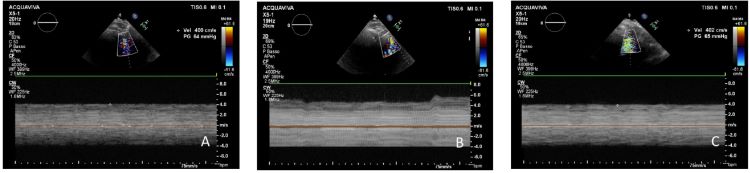

Secondly, the continuous wave colour Doppler function was activated, and the area of aliasing was identified: the continuous wave signal was filtered with the I-scan function, removing the low intensity signals and registering a continuous line. In case of thrombotic obstruction, the continuous Doppler signal showed velocity with an increase of at least 20% than normal velocity, with more frequent and wide oscillations of the line than during the Lavare™ cycle, indicating a partial and intermittent obstruction to the flow through the cannula. These temporary obstructions to blood flow had the secondary effect of increasing its velocity (see Figure 1)[5,11,12]. In addition, pulsed

Doppler modality transmitted a very harsh, frequent, and intermittent sound, typical of a thrombosis. The characteristic of this sound was similar to the murmur of aortic stenosis.

With regard to maximal blood flow velocity in the left ventricle at the near site of the inflow cannula, it was 598±42 cm/sec during thrombosis (Group B), whereas it was 379±21 cm/sec after thrombolysis (Group C) and 378±28 cm/sec at baseline control (Group A). The maximal velocities recorded at the time of thrombosis were as higher as to reach statistical significance compared to baseline and after thrombolysis recordings: Group B vs. Groups C and A (P<0.00001). On the other hand, no statistically significant different maximal blood velocities were noted in Groups A and C (P=0.5). Data and their comparisons are presented as scatter plots in Figure 2.